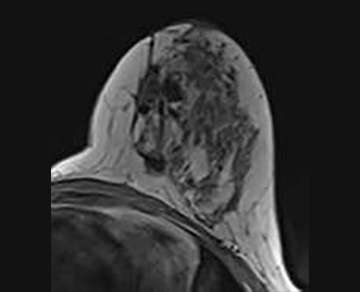

Non-mass Enhancement

Minimal non-mass enhancement (NME) adjacent to the lumpectomy site can be a normal finding up to 18 months following surgery4. A small enhancing focus or minimal linear NME may be appropriate for 6-month imaging follow-up (BI-RADS 3).

Other than the above, NME within or adjacent to the lumpectomy site is generally suspicious (BI-RADS 4). This includes new or increasing NME, nodular NME measuring greater than 5 mm, mass like enhancement, and NME in suspicious distributions such as segmental, clumped, or regional (Figure 4a and 4b)5. Enhancement kinetics are an important component of the evaluation of NME. Rapid initial enhancement and washout are most concerning for malignancy.

FIGURE 4A: T1-weighted image without fat saturation. Status-post remote lumpectomy of the left breast for DCIS. FIGURE 4B: T1-weighted post contrast image with fat saturation. Non-mass enhancement within the lumpectomy site. Biopsy demonstrated DCIS.